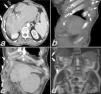

A 62-year-old man with known diagnosis of alveolar echinococcosis presented to our clinic with jaundice, abdominal pain, and draining skin lesions. Computed tomography (CT) and magnetic resonance imaging (MRI) revealed a hypodense mass with lobular contours and areas of calcification consistent with primary alveolar echinococcosis invading the right main portal vein in liver segment 7. Heterogeneous nodular masses with areas of calcification were observed on the right anterior abdominal wall and inferior chest wall and in the skin and subcutaneous tissue. In addition, destructive lytic and sporadically sclerotic changes were noted on the right pleural surfaces, ribs 7–12, and sternum xiphoid process (Fig. 1a–d). Considering the patient's diagnosis of alveolar echinococcosis, the images were evaluated as local metastasis to the skin, subcutaneous tissue, pleura, and ribs.